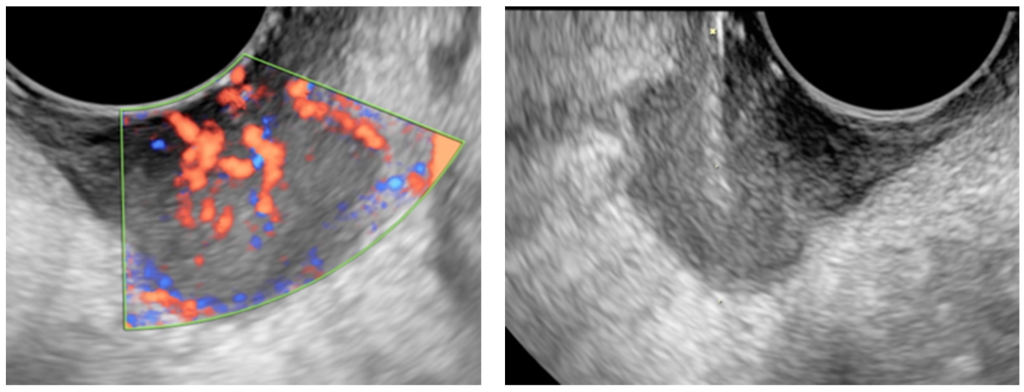

The procedure involves using a specialized needle to extract a small sample of tissue from the affected area, such as the breast, liver, kidney, or lymph nodes. Ultrasound guidance allows our radiologists to visualize the target area in real-time, ensuring that the needle is accurately positioned and that the sample is taken from the most relevant part of the lesion. This reduces the risk of complications and increases the likelihood of obtaining a diagnostic sample.

USG-guided trucut biopsy is commonly used to diagnose conditions such as breast cancer, liver tumors, kidney masses, and lymph node abnormalities. It is also valuable in cases where imaging tests like X-rays or MRIs have detected suspicious lesions but cannot confirm their nature. By providing a tissue sample for pathological analysis, trucut biopsy helps doctors determine whether a lesion is benign or malignant and guides the appropriate treatment plan.